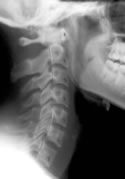

Chiropractic Improves Cervical Spine Lordosis

Identifying these ligamentous injuries, however, can be difficult. The ligaments themselves may be detected on MRI, but they cannot be seen on normal radiographs. It is more likely that the ligament injury will result in changes to the alignment of the cervical spine, and that can be detected with plain films.

A 2002 study1 compared the angle of cervical lordosis between whiplash patients and healthy controls. They found a statistically significant difference between the two groups, suggesting that whiplash injuries may indeed alter cervical spine alignment.

The authors of this current study began with 13 patients who had been in a car crash. They obtained a neutral cervical radiograph taken in the natural standing position. Then, each patient was treated by a chiropractor. The patients had an average age of 24, and the average number of chiropractic adjustments was 17.7.

After a period of care, neutral radiographs were again taken, and both the pre- and post-treatment films were evaluated by a second chiropractor who was blinded to which films belonged to which patient.

The cervical curve was measured in each of the x-rays.

10 of the 13 patients showed an increase in the cervical lordosis found on x-ray. The average increase found in the patients was 6.4°.

One patient showed no change and two patients showed a decrease in cervical lordosis.